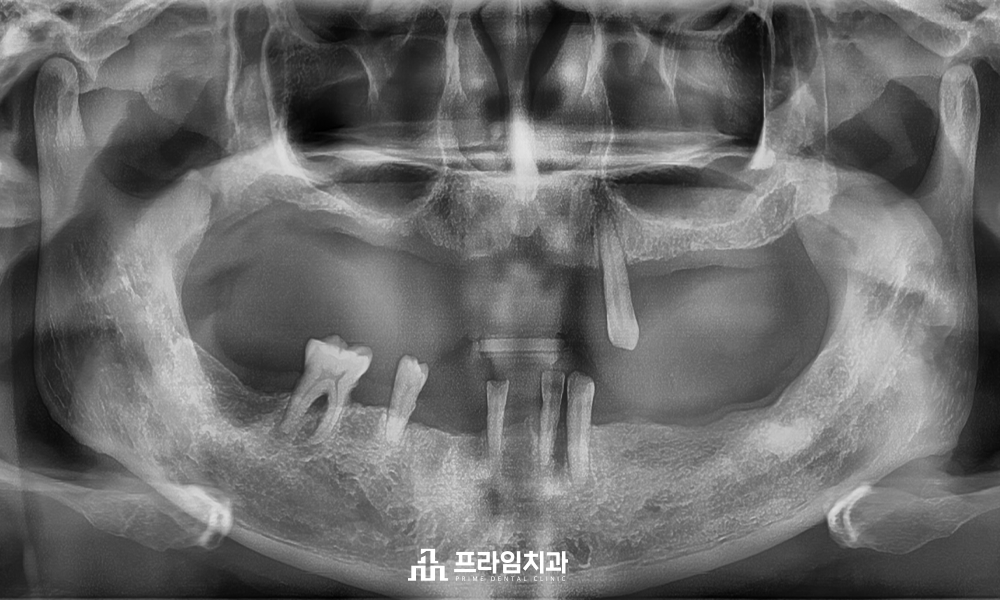

오늘은 구강 내 전체적으로

남아 있는 예후가 좋지 않은

치아들을 발치한 후

전주신시가지치과 전체임플란트를 진행하신

환.자분을 소개해 드리려고 합니다.

환자분은 기존에 틀니를 제작하여

사용하셨지만 점차적으로 남아 있는

자연치들이 흔들리고 상태가 좋지 않아져

치료 상담을 위해 내원해 주셨습니다.

잇몸뼈가 많이 흡수되어

많은 양의 뼈이식을 동반하여

최소침습 임플란트 식립을

진행하기로 하였습니다.